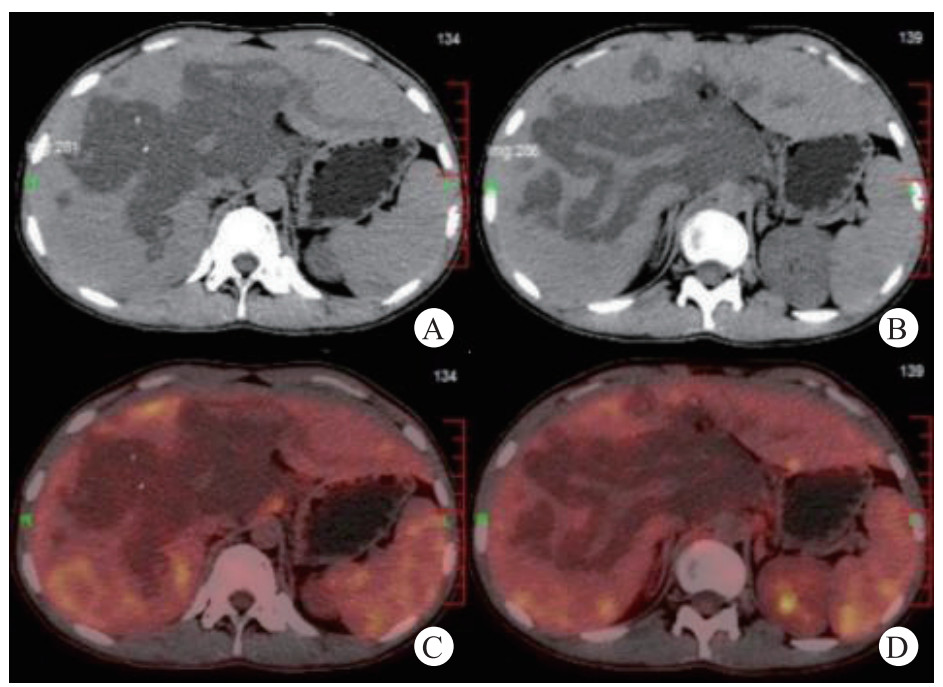

| 门静脉周围不规则长T2异常信号,沿肝内胆管、门静脉延伸 图 1 MRCP |

CT对评估淋巴管瘤体是否破裂以及评估与重要器官、大血管的走行具有重要价值。本病例肝囊性淋巴管瘤在CT上表现为呈多房状,界限清晰的多发低密度囊性病灶,囊内密度均匀;增强后囊壁轻度细线样强化,门脉期、延迟期强化明显。MRI示均匀T1WI低信号和T2WI明显高信号,囊性肿物沿组织间隙呈“爬行性生长”,强化后肝内可见纤维分隔样结构。鉴别诊断主要是肝海绵状血管瘤,肝囊肿,肝包虫病,肝转移瘤,先天性肝内胆管扩张症等疾病。